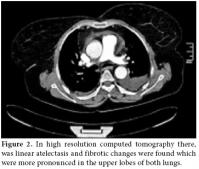

A chest radiograph showed an increased cardiothoracic index and medium to severe bilateral pleural effusion which was more pronounced in the posteroanterior right lung (figure 1).

In high resolution computed tomography (HRCT) there was linear atelectasis, and fibrotic changes were found which were more pronounced in the upper lobes of both lungs (figure 2). Mild to severe pericardial effusion was seen in echocardiography (ECHO; figure 3). Three days after 20 mg intravenous prednisolone therapy, fluid accumulation was considered to be gradually decreasing in ECHO (figure 4).

Pulmonary X-rays showed moderate and severe bilateral pleural effusion, more pronounced in the right lung, and an increased cardiothoracic index.